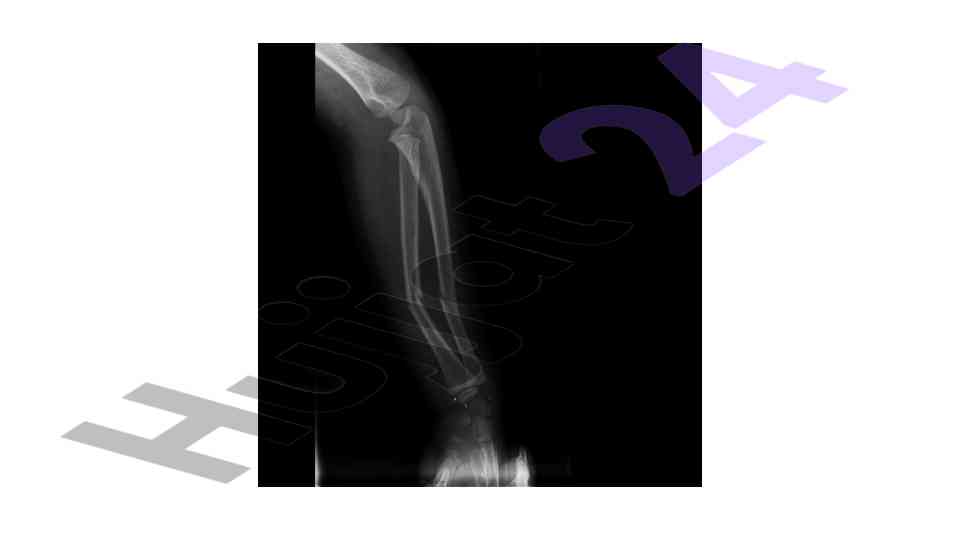

An overview of the muskuloskeletal system with a focus on pediatric applications and implications for treatment.